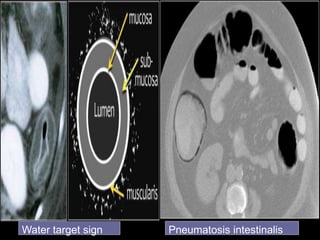

White attenuation Grey attenuation

Water target sign Pneumatosis intestinalis

Water target signPneumatosis intestinalis